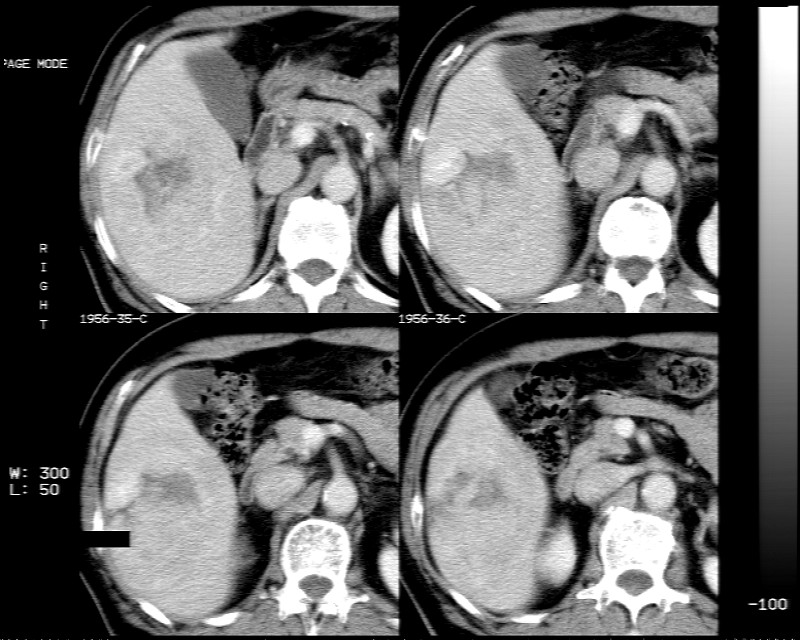

肝右叶块状低密度影,增强后动脉期病灶明显强化,门脉期及延迟期强化减低。

考虑血管瘤可能性大。

肝右叶巨大占位性病变,平扫呈低密度改变,增强扫描动脉期病灶周围强化,门脉期强化未退出,延时期病灶周边强化与肝实质接近,病灶中心在各期均可见星状不强化区;首先考虑局灶性结节增生可能性大,其次为血管瘤。肝癌不能完全排外(不首先考虑肝癌是因为强化不支持快进快出特点)。

病变总体呈快进快出改变,动脉期强化后密度不够高,肝腺瘤和fnh都接近血管密度,并且以女性多见,所以还是支持肝细胞癌。

平扫示:肝右后叶下段内见类圆形略低密度占位病灶,边界尚清楚,最大径约为102×71mm,ct值31~41hu。

动态增强扫描示:动脉期病灶显著不均性强化,病灶强化密度高于肝实质;平衡期病灶呈等密度;延迟扫描病灶密度略低于肝实质;三期均见占位病灶内有裂隙状无强化影。肝内胆管无扩张,腹膜后未见肿大淋巴结。

拟诊:肝右后叶下段内占位性病变,考虑为肝结节样增生。

建议进一步检查(mri/或穿刺活检),不排外肝ca。